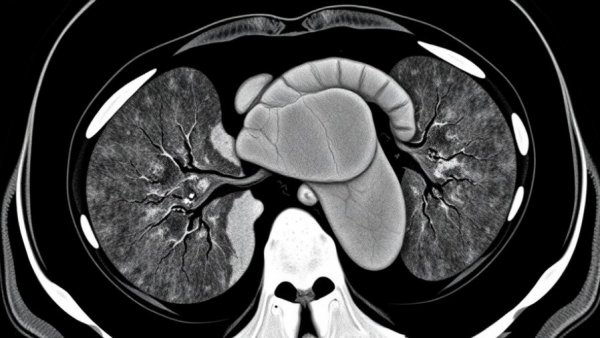

AI-Powered Cardiovascular Screening Michigan showing CT scan of heart highlighting calcification.

Cardiovascular diseases remain the leading cause of death in the United States. Many individuals are unaware of their risk factors until it's too late. McLaren's screening program aims to bridge this gap by utilizing routine chest CT scans to identify markers of heart disease that traditionally go unnoticed. Through partnerships with Bunkerhill Health, their advancements in imaging have introduced the ability to detect both incidental coronary artery calcium (iCAC) and incidental aortic valve calcium (iAVC), key indicators of heart conditions such as coronary artery disease and aortic stenosis.

This groundbreaking program streamlines the process of heart disease screening by analyzing data from chest CT scans that patients have already undergone for unrelated medical reasons, such as lung cancer screenings. This not only speeds up the detection process but also eliminates the need for additional imaging, making cardiovascular care more accessible to a larger population.